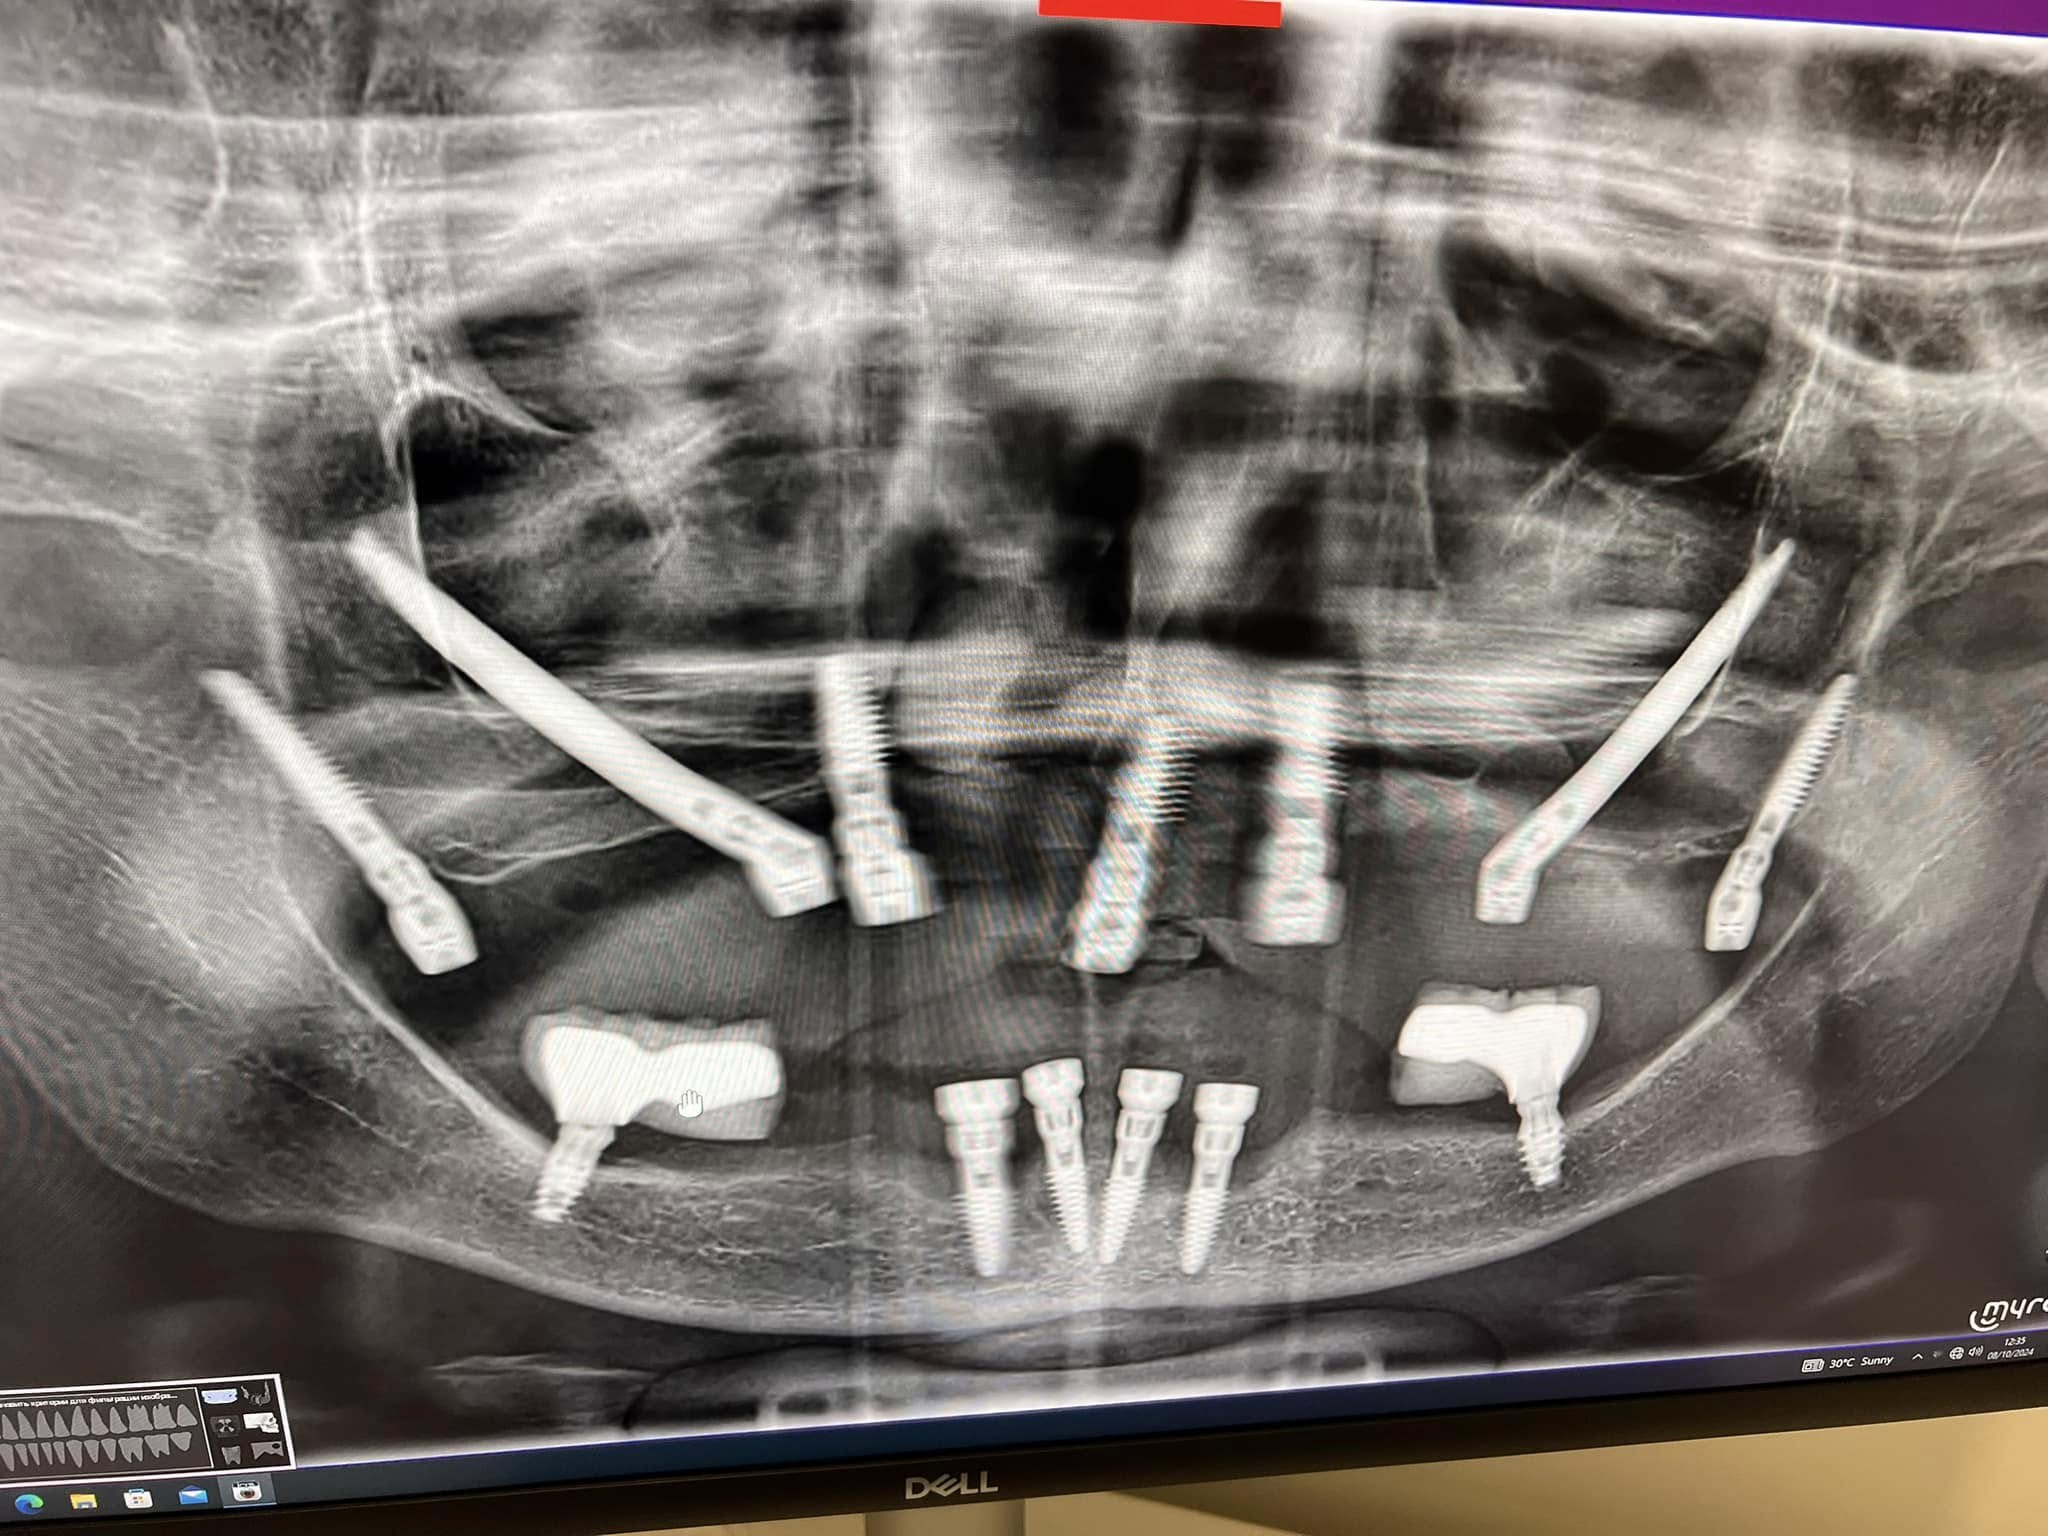

תהליך האבחון במרפאה מתחיל בפגישת ייעוץ אישית עם ד"ר בירשאן, הכוללת בדיקה קלינית מקיפה, צילומי רנטגן מתקדמים במידת הצורך, והצגת תוכנית טיפול מפורטת תוך מתן מספר חלופות טיפוליות. כל מטופל מקבל הסבר מלא על האפשרויות, סיכויי הצלחה, יתרונות וחסרונות של כל גישה, מתוך מטרה לאפשר בחירה מושכלת וביטחון מלא בטיפול.

בהחלט. ד"ר בירשאן מחזיק בהסמכות הגבוהות בעולם בתחום השתלות דנטליות ומבצע שיקום מקרים מורכבים גם במצבים של ספיגה חמורה של עצם הלסת. המרפאה עושה שימוש בטכנולוגיות שתלים מתקדמות כמו שתלים בזאליים ושתלים דיסקיים, המאפשרים פתרונות גם במצבים שבעבר נחשבו בלתי ניתנים לשיקום.